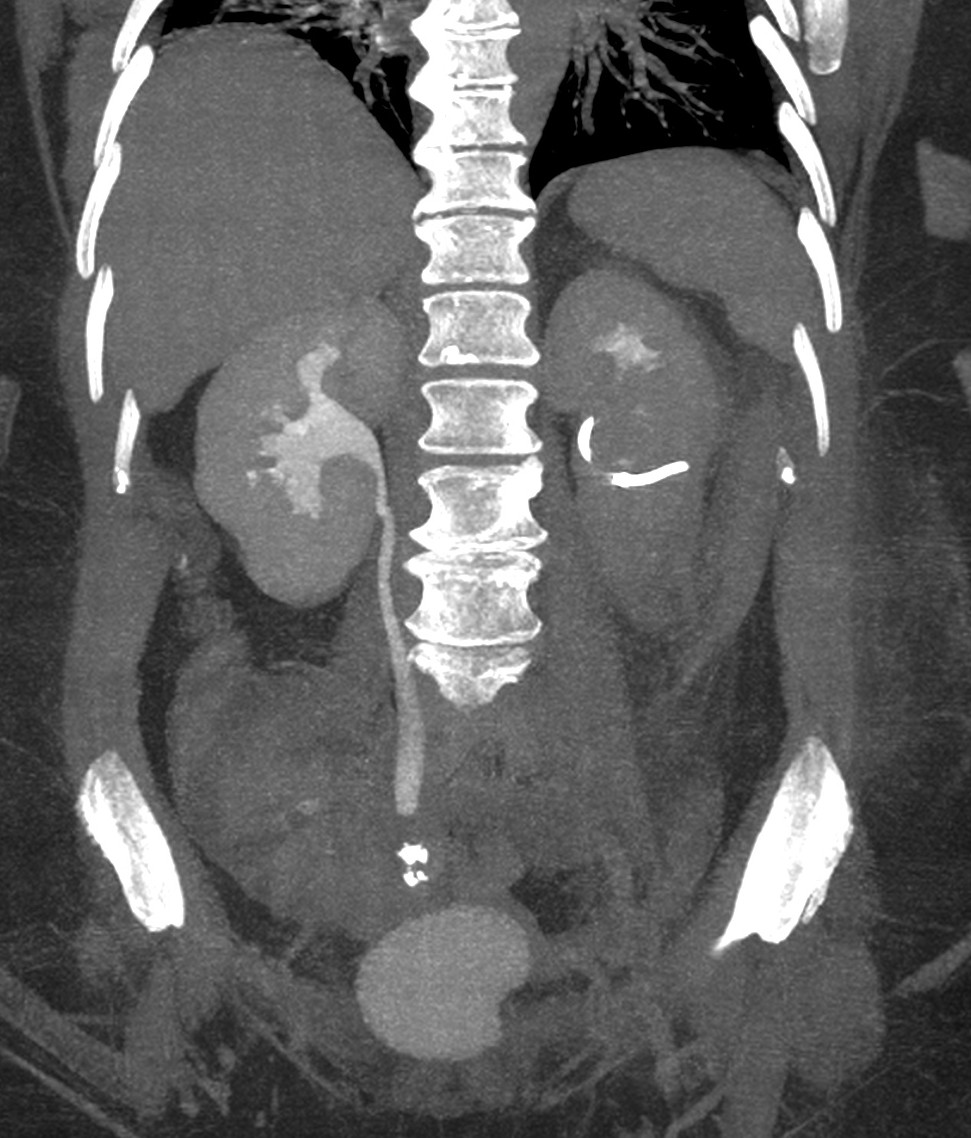

CASO CLÍNICO: Recopilatoción.

Paciente de 59 años con antecedentes personales de Cá de vejiga.

Se le realiza una Uro-Tc por seguimiento al año, aunque en esta ocasión el paciente refiere episodio de hematuria.

Tras el tratamiento de la recidiva y nefrostomía para la hidroureteronefrosis, vuelve acudir al hospital a los 9 meses por episodio de dolor en FD y malestar general. Se realiza una ecografía de urgencias.

Se realiza nueva TC bifásico abdominopélvio y Uro TC.

- Paciente con numerosas recidivas por Cá vejiga.

- Ha desarrollado un tumor metacrónico en pelvis renal derecha, también responsable de la hidroureteronefrosis.